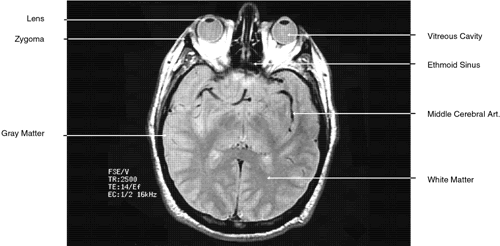

Fig. 7. Axial T1-weighted magnetic resonance imaging through midglobe.

During MRI, the T1 and T2 differences between various tissues can be weighted to enhance the MR image produced. Essentially, this process increases the contrast between adjacent tissue structures and improves their visualization. This is ac-complished by varying within a particular pulse sequence either the repetition time (TR) betweenapplied radiofrequency pulses and the echo time(TE), or the time between the applied pulse andthe detection of the produced signal. A short TRfavors tissues with a short T1, such as fat. For exam-ple, with a TR of 300 msec, tissues will be enhanced in the following order: fat > white matter > gray matter > uvea > aqueous > vitreous, optic nerve, muscle > cortical bone. The reason for the intense response of fat is that with a short T1 it can almost completely recover its resting state between pulses. This enables it to respond again to the next pulse. Generally, T1-weighted images have a pulse sequence with a TR of 200 to 1,000 msec as well as a short TE (20 to 25 msec) (Fig. 7). The longer a particular tissue's T1, the less it can respond to the next pulse, because fewer of its protons have returned to a resting state. Therefore, its MR image is less intense. Lengthening the TR will allow more protons time to relax until the signal produced no longer depends on a tissue's T1. The image produced when the TR is long (2,000 to 2,500 msec) is “proton density”-weighted (Fig. 8). When this is the case, tissues with the highest proton density (e.g., gray matter and old hemorrhage) produce the most intense signal. In both T1- and proton density-weighted images, the TE is short (20 to 25 msec). The clearest anatomical delineation between tissues is provided by highly T1-weighted images with TR values between 300 and 500 msec.25,26

Fig. 8. Axial proton-density magnetic resonance imaging through midglobe.

T2-weighted images can be produced at the same time as proton density images. In this case both the TR and TE are prolonged. By allowing all tissues to relax maximally, the most intense signal will be produced by the tissue with the longest T2 (that is, the tissue that remains coherent the longest). A particular tissue's T2, which typically ranges between 25 and 150 msec, is usually much shorter than its T1. To obtain a T2-weighted image, both the TR (>2,000 msec) and the TE (50 to 150 msec) are long (Fig. 9). In such cases, vitreous and cerebrospinal fluid give the most intense images and fat, white and gray matter, bone, and air give the least intense images.

Fig. 9. Axial T1-weighted magnetic resonance imaging through midglobe.